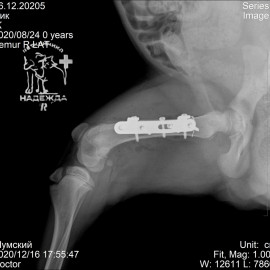

В нашу клинику обратились с жалобами на хромоту на правую заднюю лапу. После проведённых исследований был поставлен диагноз: перелом правой бедренной кости. Была проведена операция - остеосинтез правой бедренной кости.

Снимок 2-3 после операции